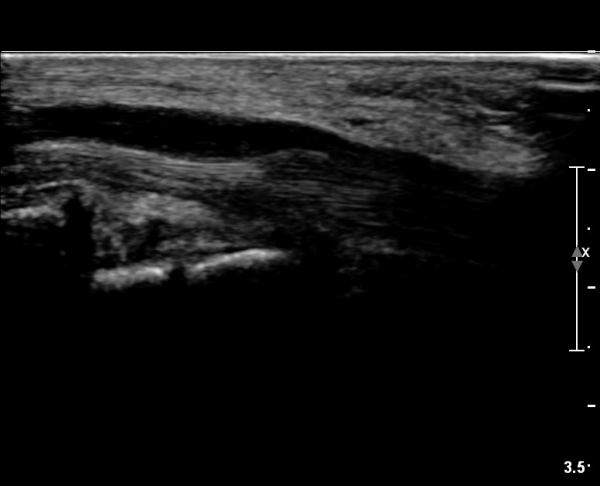

ÃÊÀ½ÆÄ ¼Ò°ß :  ¼Õ¸ñ±ÙÀ§ºÎ Ⱦ´Ü¸é°Ë»ç¿¡¼­ ¼Õ¸ñ±¼±Ù°Ç(FCR)°ú Ç¥Ãþ ¼Õ°¡¶ô ±ÁÈû±Ù(FDS) »çÀÌ¿¡

Á¤Á߽ŰæÀÌ Á¤»óÀûÀÎ ¾ç»óÀ¸·Î º¸ÀÓ(»çÁø 1).

Å½ÃËÀÚ¸¦ ¸»´ÜÀ¸·Î À̵¿ÇÏÀÚ  Á¤Áß½Å굥 ¿äÃø ÀϺΰ¡ Àú¿¡ÄÚ Á¾±«·Î °üÂûµÊ(»çÁø 2).

ÀÌ·± ¸ð½ÀÀº ¼Õ¸ñÀÇ ¿ù»ó°ñ ºÎÀ§(»çÁø 3, 4)¸¦ Áö³ª ¼ö±Ù°ü ±ÙÀ§ºÎ ±îÁö À̾îÁü(»çÁø 5).

ÇÏŰ½ºÆ½(°íÁÖÆÄ) ŽÃËÀÚ¸¦·Î °üÂûµÈ ¸ð½À¿¡¼­ Á¤Áß½Å°æ ºÎºÐ ½Å°æ´Ù¹ßÀÇ Àú¿¡ÄÚ

º¯È­°¡ ¶Ñ·ÈÇÔ(»çÁø 6, 7).

Á¤Á߽Űæ Á¾´Ü¸é°Ë»ç¿¡¼­µµ ¼Õ¸ñ ¸»´ÜºÎ¿¡¼­ ¼ö±Ù°ü ±ÙÀ§ºÎ±îÁö À̾îÁø Àú¿¡ÄÚ

Á¾¾çÀÌ °üÂûµÊ(»çÁø 8, 9, 10, 11).